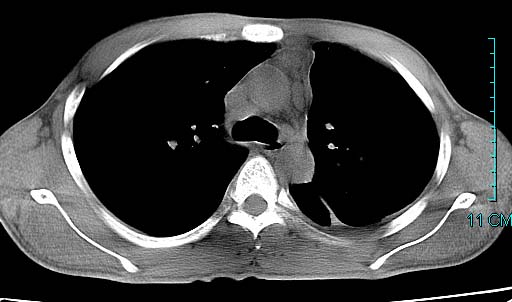

以下是引用ctkz987在2006-3-28 13:04:00的发言:[br]左侧胸腔积液穿刺后多发气液平(多房性),结合临床有高热不除外合并感染。

以下是引用qian在2006-3-28 14:32:00的发言:[br]左肺下叶大片状阴影,密度不均,见有条片影和空洞及气液平,少量胸腔积液伴有胸膜增厚,从图像看积液密度比水的密度高,结合病史,考虑左下肺化脓性炎症伴有脓胸。

以下是引用wawaquan在2006-3-28 22:25:00的发言:[br]左上肺舌段多发斑片影。结合“男24y咳嗽咳痰气促伴高热(38.5--39.5)20多天”及穿刺史,[br]考虑1 左下肺化脓性炎症;2脓胸。

以下是引用乡医在2006-3-28 18:37:00的发言:[br]左侧多发液气平面结合患者男24y咳嗽咳痰气促伴高热(38.5--39.5)20多天,查胸水:ldh239.3,总蛋白59.19,tb-ab阴性,利凡它试验+,红c2.7*109,白c1.08*109,分类淋巴92%分叶8%,考虑1脓胸2肺隔离征感染